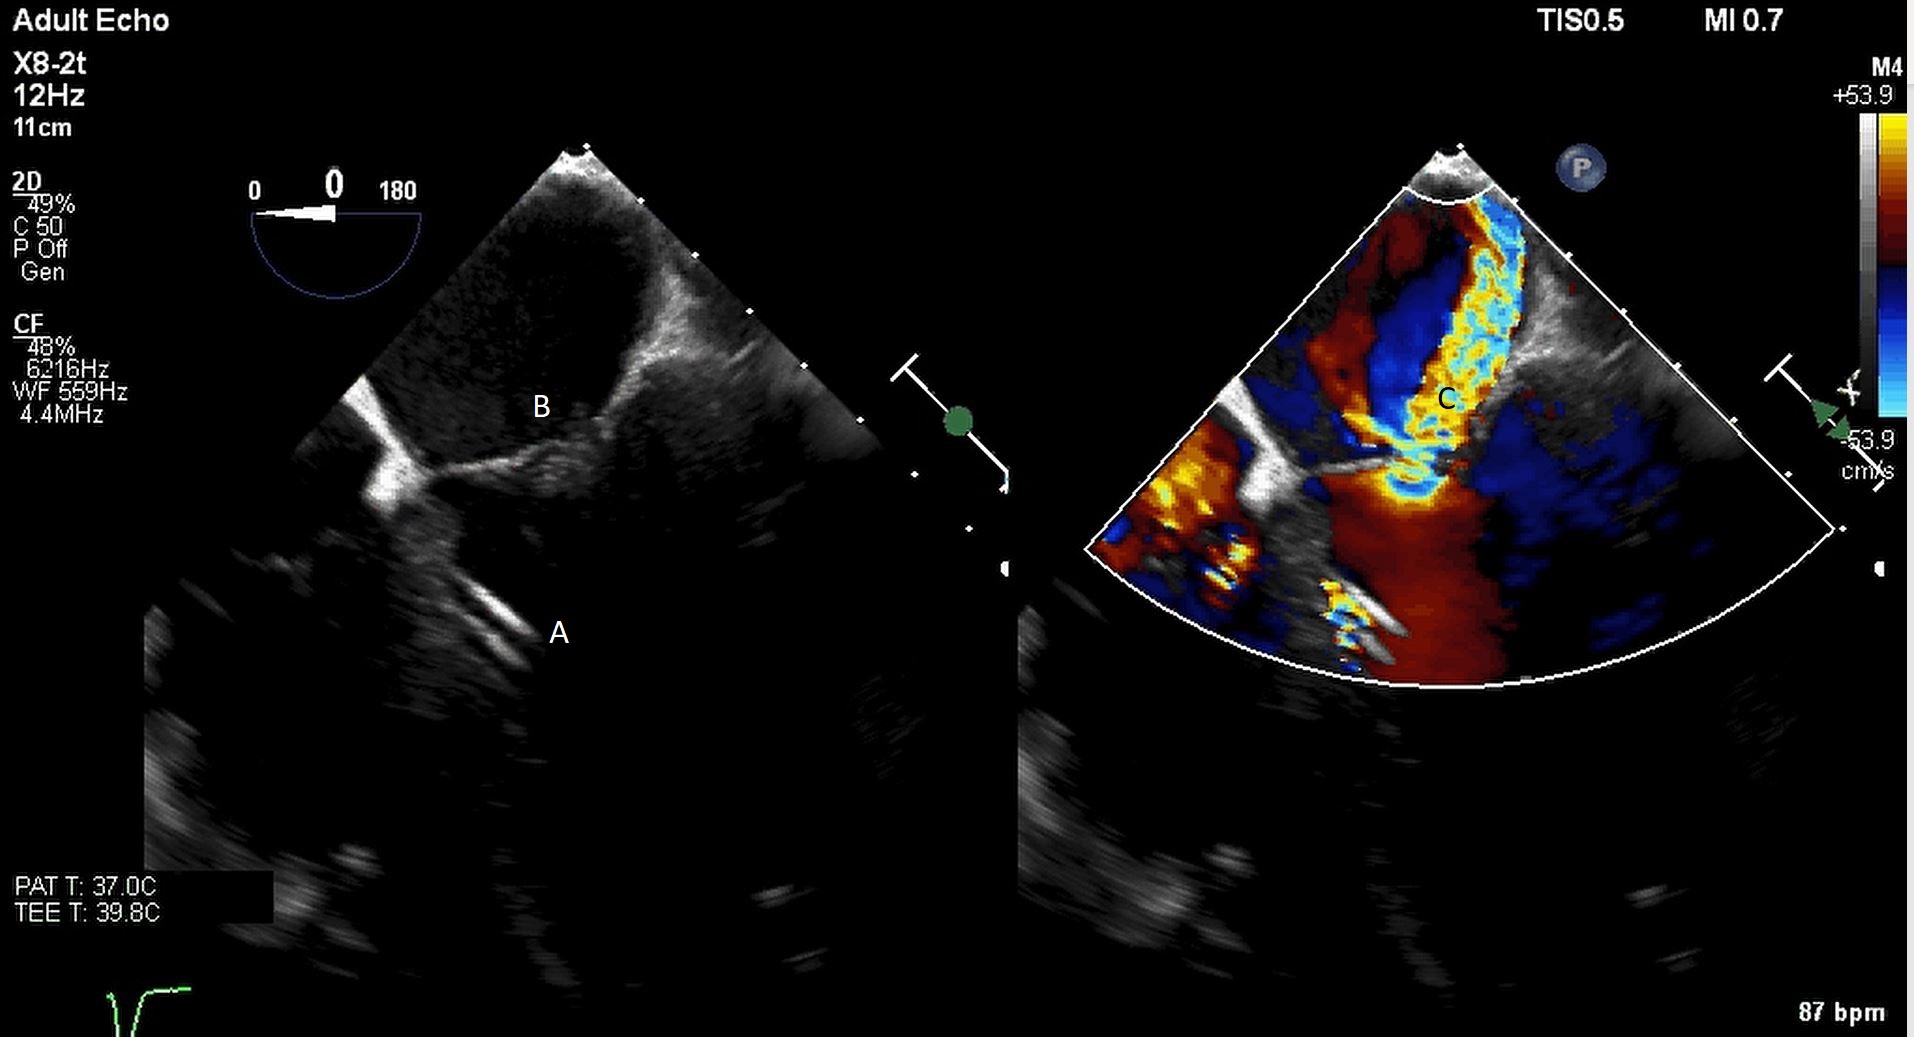

Impella (A) in the LV cavity caused disruption and damage to subvalvular apparatus resulting in flail segment (B) of the mitral valve.

Fig. 4.Impella (A) placement causing disruption and damage to subvalvular apparatus resulting in mitral valve flail (B) and mitral regurgitation (C).